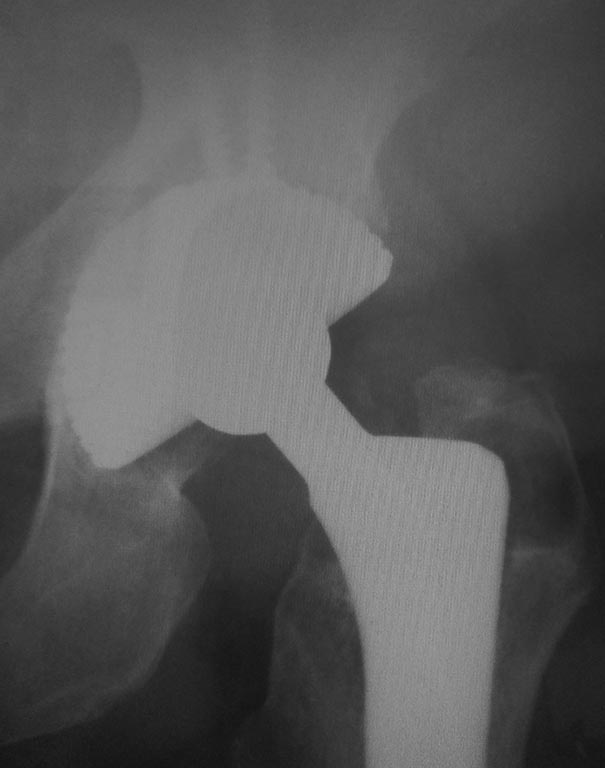

Р-грамма 2011 г

Р-грамма 2019 год

Децентрация головки эндопротеза в вертужной впадине? Доброго дня, уважаемые коллеги. В настоящее время на консервативном лечении находится пациент 1951 г.р., мужчина. В 2009 и 2010 гг.по поводу коксартроза выполнено тотальное эндопротезирование правого и левого тазобедренных суставов. В течение длительного времени беспокоит боль в левом тазобедренном суставе, периодически возникают эпизоды, которые пациент расценивает как подвывих, устраняет эти ощущения ротацией н/конечности. Рентгенограмм в момент "вывиха" не выполнялось. На контрольных рентгенограммах отмечается децентрация головки эндопротеза слева, смещение головки в краниальном направлении. Пациент консультирован в нашем ведущем учреждении, убедительных данных за нестабильность эндопротеза не выявлено, рекомендации- лечение консервативное. Однако, учитывая рентгенологическую картину, нельзя ли предположить износ полиэтилена? Каковы рекомендации в плане дальнейшей тактики?